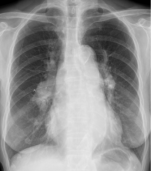

3、肺淤血:肺静脉回流受阻

X线表现:上下肺静脉管径比例失调,上肺静脉扩张增粗,下肺静脉收缩变细肺纹理增多、增粗且模糊,肺门影增大模糊,搏动减弱肺野透光度降低

Kerley B”线:肋膈角区水平走行的细线状影,宽1- 3mm,长20-30mm(慢性左心衰,小叶间隔水肿)结合病理生理详细分析形成Kerley B的原因、过程,并给多个病例,明确让学生掌握。并围绕肺淤血给出影像学征象的思考题。

肺泡性肺水肿:液体渗入肺泡

X线表现:一侧或两侧肺野有片状模糊影,以中内带多见,典型者两侧肺门区大片模糊影呈蝶翼状合并间质性肺水肿病变阴影,短期内变化大,来去迅速